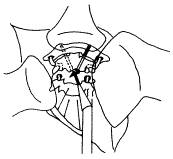

扪及寰椎前结节,沿椎体前正中线切开C1~C3椎前筋膜,骨膜下剥离,切除少量C2~3椎间盘前部,显露枢椎椎体前下缘。于前下缘中点两侧各1mm处,以3.2mm钻头(使用带20°倾斜角的微型电钻),分别按术前计划中制定的螺钉置入角度,向外、向后钻入,经寰枢关节内侧份进入寰椎侧块,至侧块上关节面骨皮质下停止(图3)。测深器测出钉道的全长及其分别在枢椎椎体和寰椎侧块中的长度,选择恰当长度的直径为3.5mm的部分螺纹松质骨螺钉拧入。注意使螺纹全部拧入侧块中,应用拉力螺钉原则,在寰枢关节之间产生加压作用。取出整段颈椎,摄正侧位片(图4)。

图3 手术示意图

图4 手术模型术后正侧位X线片